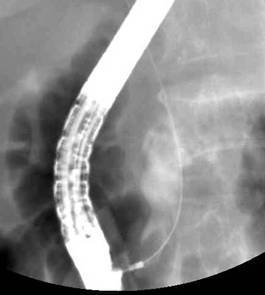

둘째는 삽관된 카테터로 방사선 조영제를 주입하여 담관 또는 췌관에 대해 방사선 투시 및 촬영을 하여 진단을 하고 필요하면 유두부를 절개하여 담관-췌관의 병을 치료하는 것이다. 이런 시술을 내시경 역행성 담도-췌관 조영술(ERCP)이라고 한다. 즉, 이 검사는 내시경 검사와 방사선 검사 둘 다를 포함한다. 따라서 ERCP를 시술하는 의사는 내시경 술기와 투시 조영술 모두에 전문가이어야 한다. 또한 ERCP를 이용한 중재적 시술은 상부소화관내시경 검사보다 시간이 더 걸리고 중증의 합병증 위험이 있어서 모든 내시경의사가 ERCP를 할 수는 없고 전문적인 수련 과정을 이수한 후에 시술을 하는 것이 바람직하다.

주로 돌이나 종양 때문에 담관이 막혀 염증이 발생하는데 담관염이 확인되면 먼저 응급으로 내시경을 이용하여 (ERCP) 쓸개즙을 배농시켜야하며 때에 따라서 막힌 부위를 뚫어 주어야합니다.